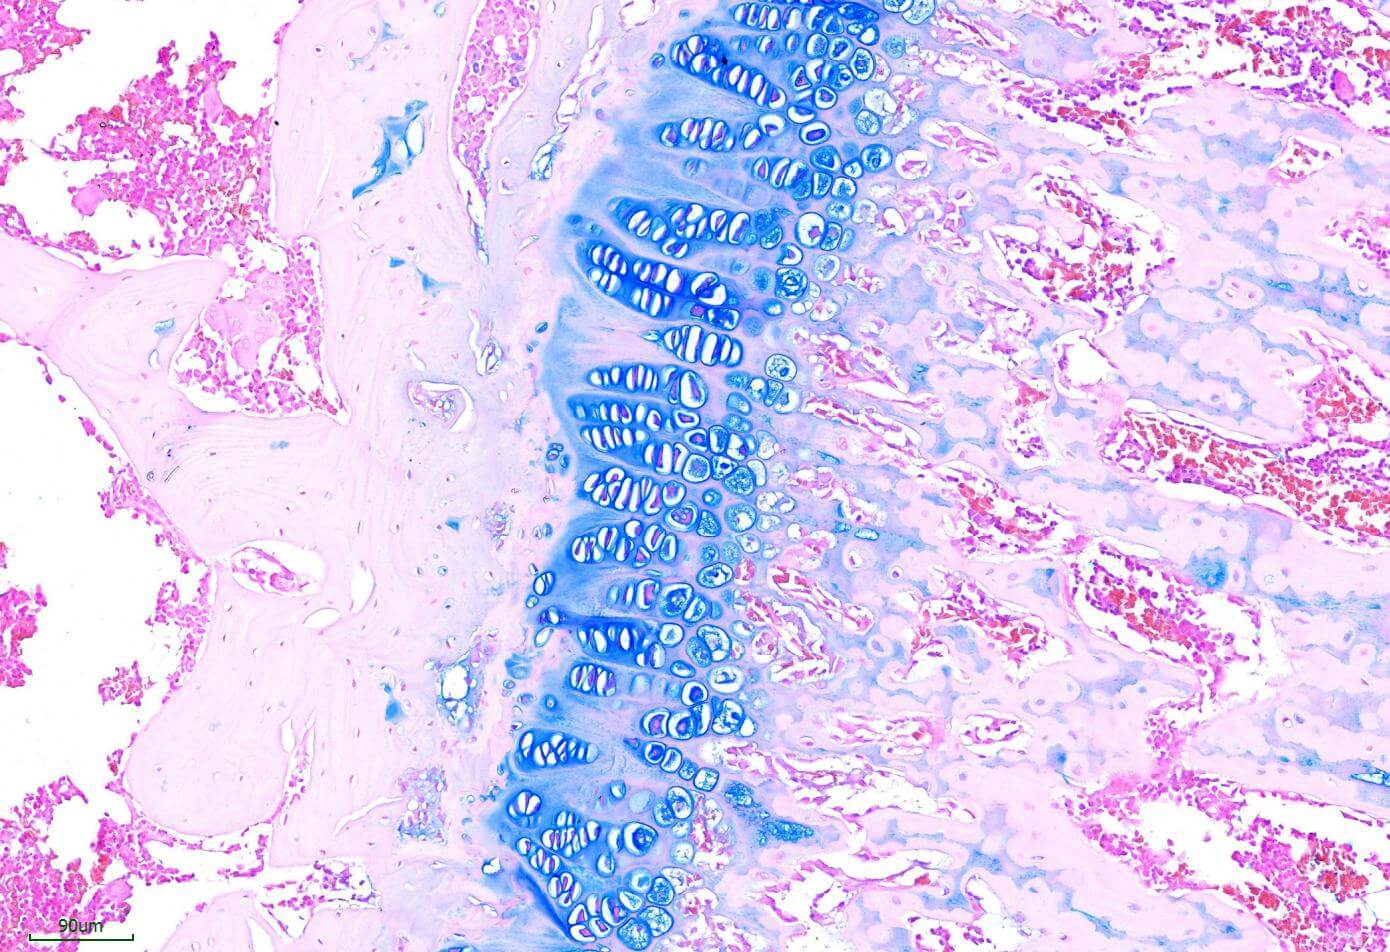

Alcian blue